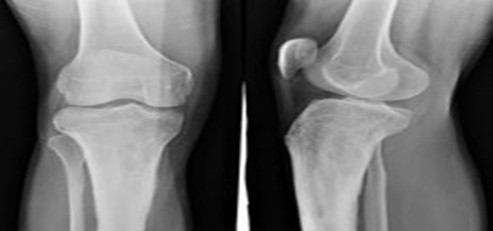

常见四肢骨折的分类之六、股骨颈骨折

常发生于老年人,以女性为多。由于跌倒时下肢遭受扭转暴力引起。头下型和经颈型,由于股骨头的血液循环大多中断。易出现骨折不愈合或股骨头缺血性坏死;基底型,因骨折端血运良好,骨折较易愈合。表现特点:患肢有缩短、外旋,大转子明显突出,患髋压痛,轴位扣击时有震痛,但嵌插骨折病人仍能行走。病人年龄较大,卧床时间较长,容易出现褥疮、坠积性肺炎及泌尿系病人等并发症。》》》专家在线,点击免费咨询、预约